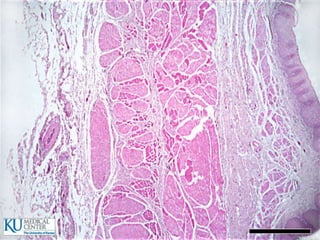

Aparato digestivo tubular

 Mucosa

 Submucosa

 Muscular

 Serosa

Mucosa

 Formada por:

1. Membrana epitelial superficial

2. Lámina propia

3. Muscularis mucosae

 Contiene vellosidades y criptas que incrementan la

capacidad de absorción y secreción

Intestino delgado

 720 cm de longitud

 Duodeno: 20 cm

 Yeyuno

 Íleon

Especializaciones superficiales de

la mucosa

 Pliegues circulares (válvulas de Kerckring)

 Vellosidades y criptas

 Microvellosidades